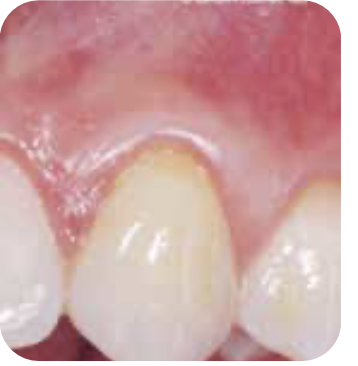

🌿 잇몸 상태 비교

AFTER염증 감소와 잇몸 건강 회복을 확인할 수 있습니다